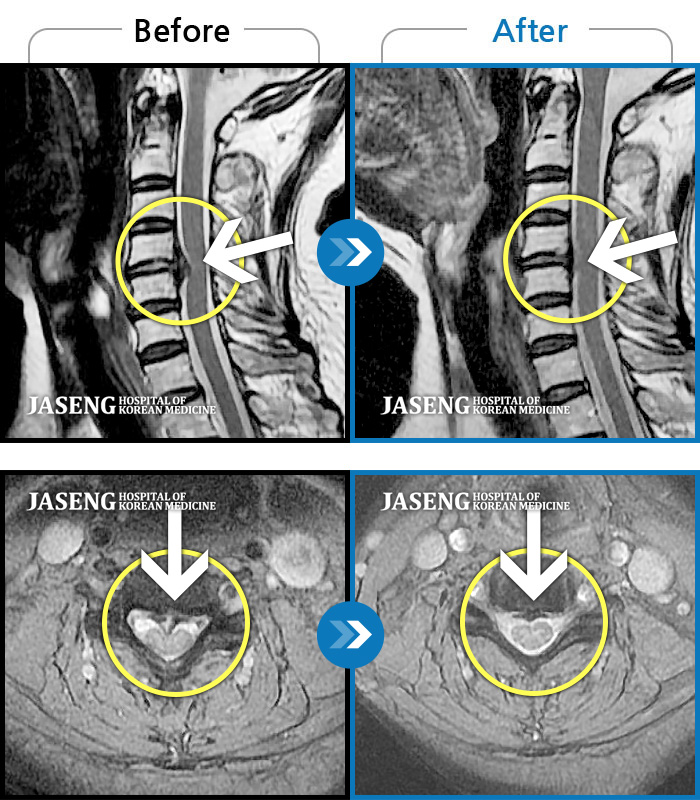

Before

After

환자에게 사전 동의를 받아 동일 조건에서 촬영되었습니다.

개인에 따라 치료 후 부작용이 발생할 수 있으니 의료진과 상담 후 치료를 진행하시기 바랍니다.

모든 자세에서 지속적으로 좌측 엉치, 허벅지, 종아리 후면, 외측, 발가락 끝까지 저리고 아프다.

양측 허리의 묵직한 통증 및 기침 시 증상이 심화되어 내원하셨습니다.